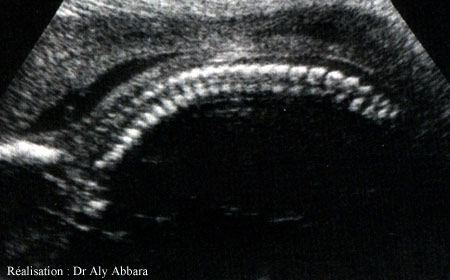

Coupe sagittale postérieure fœtale montrant

le rachis (la colonne vertébrale)

24 semaines d'aménorrhée